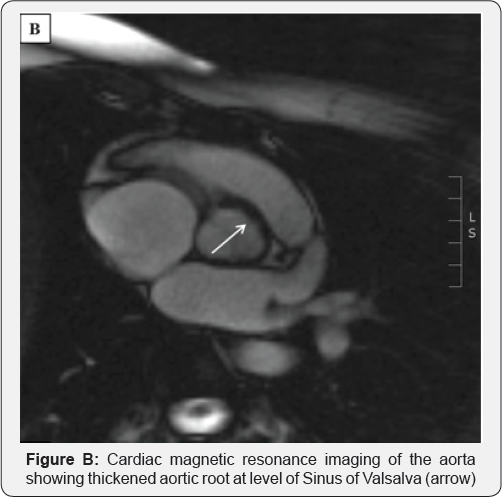

Over the next 18 months, this lady presented twice with worsening angina. On the first occasion, the LMS artery stent was patent and a new ostial RCA stenosis was seen. IVUS showing adventitial disease and the RCA stenosis was treated with a DES. On the second occasion, there was severe in-stent re-stenosis of both the LMS and RCA stents. Echocardiography demonstrated moderate AV regurgitation with cusp thickening. An MRI showed focal aortitis and a thickened aortic root (Figure B). She underwent coronary artery bypass grafting (CABG) and replacement of the AV and aortic root. Intra-operatively, the aortic root was thickened with an inflamed adventitia, in keeping with an aortitis (Figure C). Histology showed mixed inflammatory cell influx and multinucleate giant cells (Figure D), consistent with Giant Cell Aortitis with involvement of the AV.